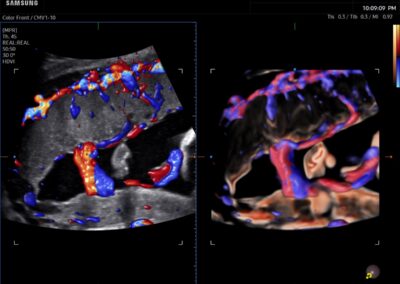

Procedural Services

Comprehensive, advanced and expert MFM care for high-risk pregnancies